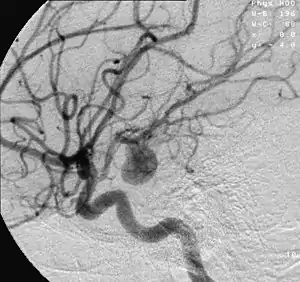

Aneurysm in a cerebral artery,

one cause of hypoxic anoxic injury (HAI).

2. Focal cerebral ischemia – A stroke occurring in a localized area that can either be acute or transient. This may be due to a variety of medical conditions such as an aneurysm that causes a hemorrhagic stroke, or an occlusion occurring in the affected blood vessels due to a thrombus (thrombotic stroke) or embolus (embolic stroke).[20] Focal cerebral ischemia constitutes a large majority of the clinical cases in stroke pathology with the infarct usually occurring in the middle cerebral artery (MCA).[21]